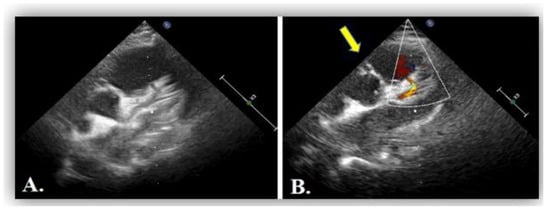

2. Case Report #1